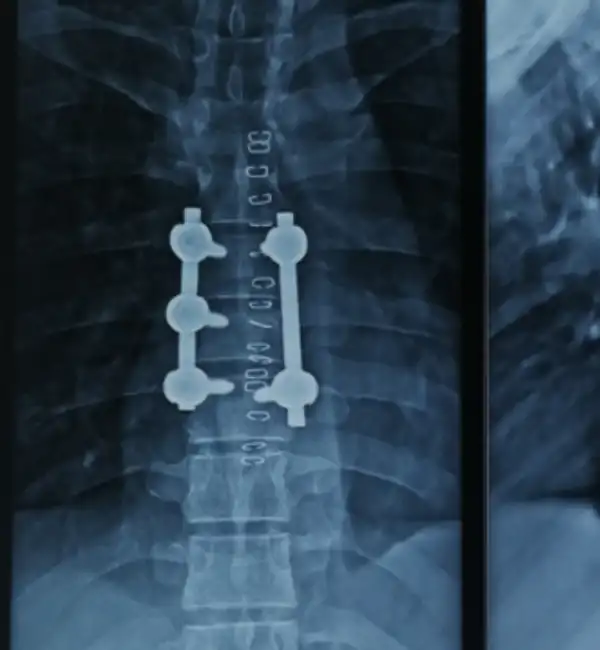

T7 fracture Post Op

T2 Fracture Post Op